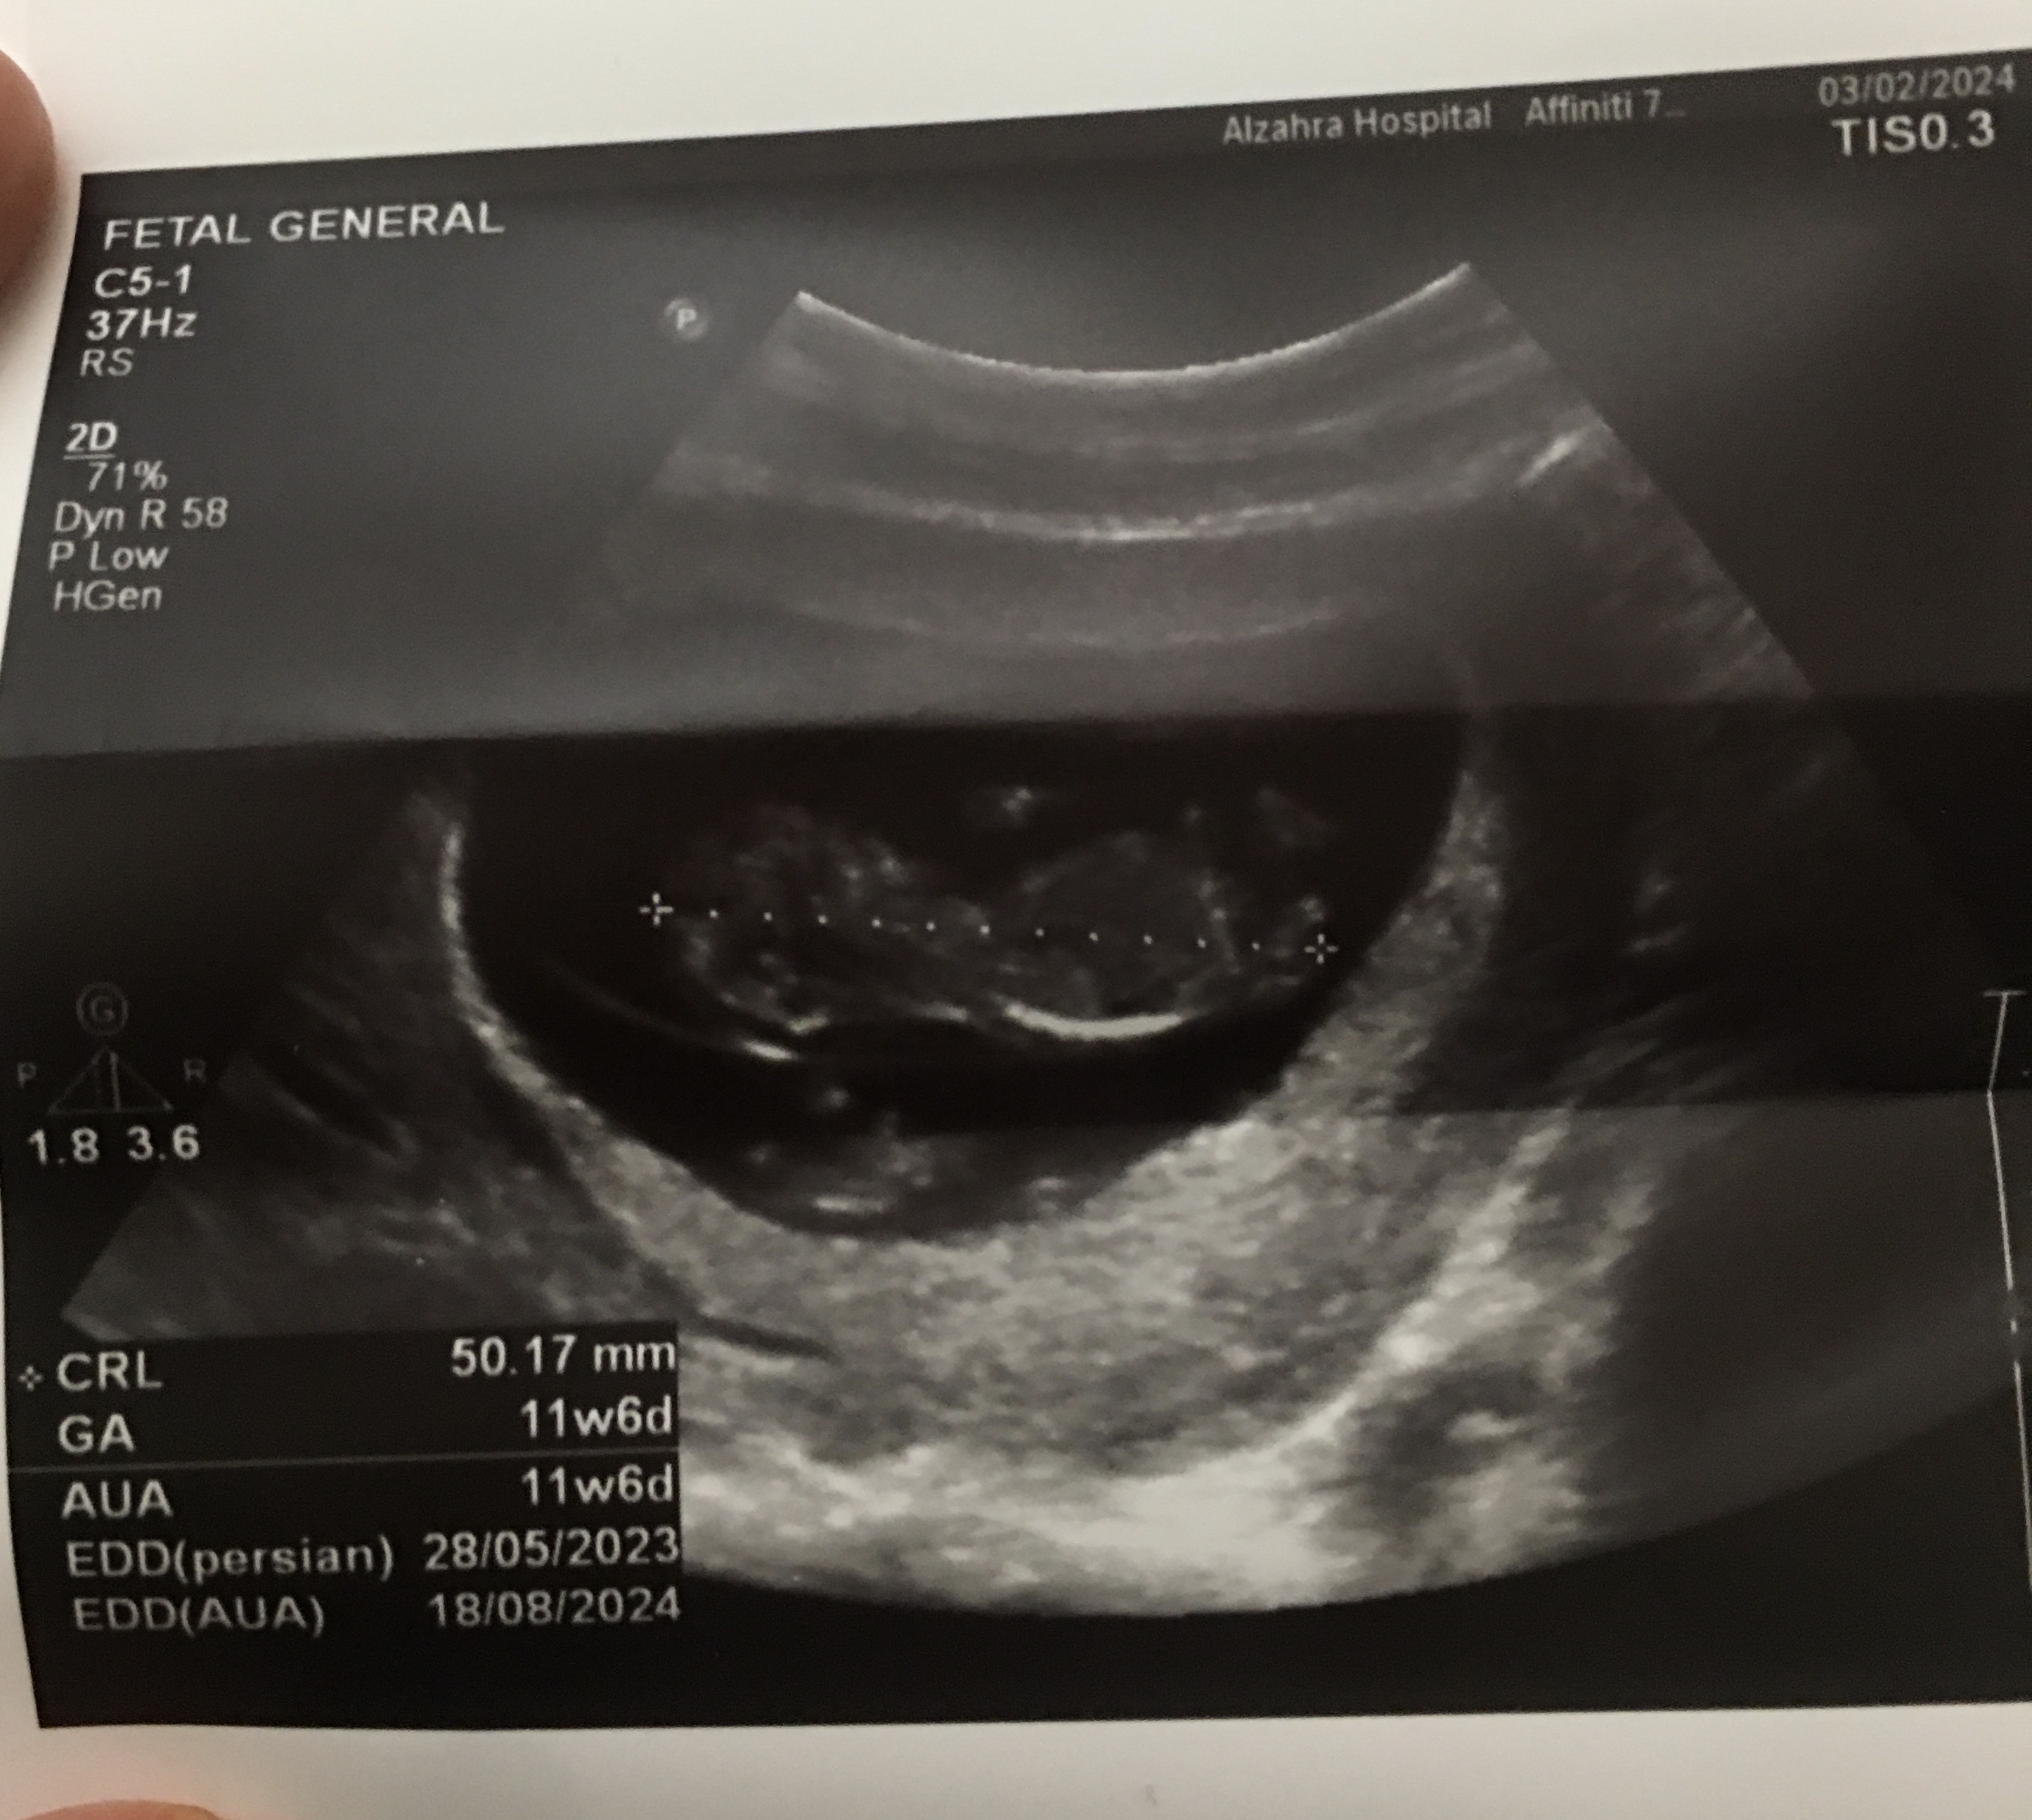

msal مدیر استارتر عضویت: 1401/06/14 تعداد پست: 545 عنوان خانومای وارد میتونین جنسیت دوقلوهای منو حدس بزنین😊 300 بازدید | 19 پست میشه بگین ممنون 1402/11/14 | 16:17 0 نفر لایک کرده اند ... گزارش تاپیک نامناسب